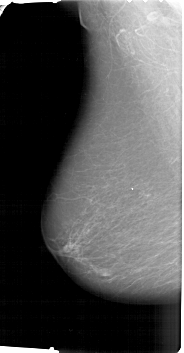

A_1501_1.RIGHT_MLO

A_1501_1.RIGHT_CC

RIGHT_CC LINES 5626 PIXELS_PER_LINE 3016 BITS_PER_PIXEL 12 RESOLUTION 43.5 NON_OVERLAY

RIGHT_MLO LINES 6331 PIXELS_PER_LINE 3646 BITS_PER_PIXEL 12 RESOLUTION 43.5 OVERLAY